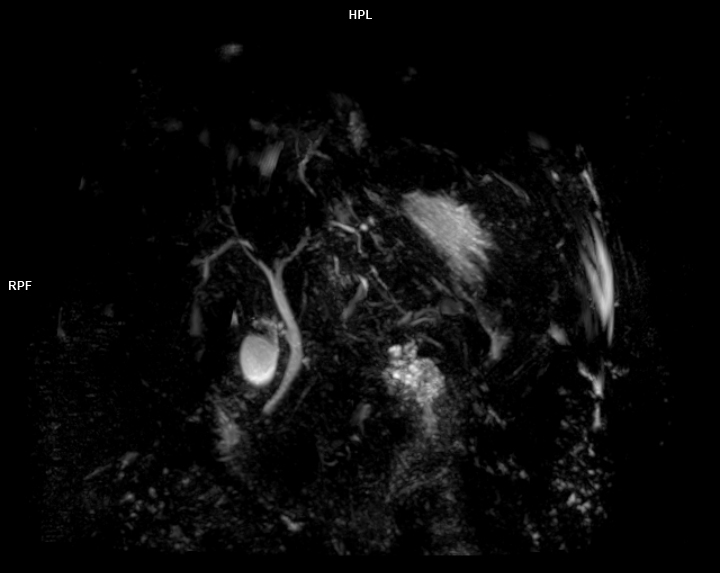

• MRCP(Kolanjiyopankreatografi)

• 3 TESLA MR ÇEKİM GÖRÜNTÜLERİ

3 Tesla MR Çekim Görüntüleri

• 3 Tesla MR Çekim Görüntüleri